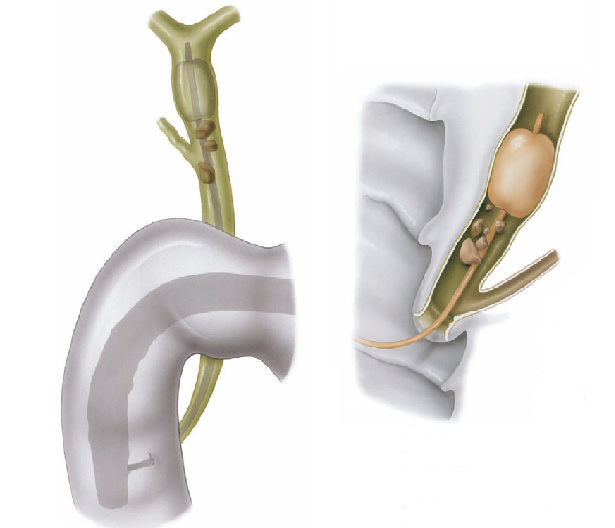

O que é um exame de CPRE (colangiopancreatografia retrógrada endoscópica)?

A CPRE é um procedimento que pode ser feito para examinar o fígado, vesícula biliar, vias biliares e o pâncreas. O fígado é um órgão que, entre outras coisas, produz um líquido chamado bile que auxilia a digestão. A vesícula biliar é um órgão pequeno, em forma de pêra, que armazena a bile até que seja necessária para a digestão. Os ductos biliares são canais que transportam a bile do fígado para a vesícula biliar e duodeno. Estes ductos são chamados algumas vezes de árvore ou via biliar. O pâncreas é um órgão que produz substâncias químicas que ajudam a digestão.

Com o paciente sedado, o aparelho é introduzido pela boca e passa através do esôfago e do estômago para o duodeno, local onde fica posicionada a papila duodenal.

Para o exame, o médico utiliza um tubo flexível e iluminado chamado duodenoscópio, que possui uma câmera na lateral do aparelho, diferente do endoscópico padrão que possui a câmera na frente do aparelho.

O médico verifica a abertura do tubo de drenagem de bile do fígado. Este tubo de drenagem é chamado de ducto biliar comum. Drena bile do fígado e suco pancreático para o duodeno para ajudar na digestão das gorduras. O orifício de saída do ducto biliar no parede do duodeno chama-se papila duodenal.

Durante o exame o médico passa de um pequeno cateter (tubo) dentro do ducto biliar comum e injeta um contraste que pode ser visto com um exame de raio-X. A via biliar e eventualmente o pâncreas podem então ser examinados para anormalidades.

A CPRE pode ser utilizada para o tratamento de pedras ou bloqueios nos canais biliares. Seu médico pode usar alguns acessórios para fazer um pequeno corte na parede do intestino, na abertura do duto biliar comum para alargar a abertura da papila duodenal. Este procedimento chama-se papilotomia endoscópica.

Após este procedimento, pode ser possível a retirada de cálculos da via biliar, permitindo assim o retorno normal da drenagem da bile do fígado para o duodeno.

Pode-se também realizar a passem de prótese através da abertura, para drenar a via biliar em caso de grande cálculos ou tumores que possam estar obstruindo a região.

Durante a CPRE, após a cateterização da via biliar e infusão de contraste, realiza-se o RX, que pode mostar cálculos (pedras) que podem estar obstruindo a saída da bile e causando os sintomas no paciente.

Após este diagnóstico realiza-se o procedimento de papilotomia endoscópica, para poder alargar a saída do canal da bile. Com isto pode-se retirar as pedras da via biliar e permitir o retorno normal da drenagem da bile do fígado para o duodeno.

Geralmente a simples abertura da saída do canal da bile não é suficiente para que o cálculo saia. Nestes casos precisamos inserir instrumentos através do duodenoscópico como cestas ou balões para varrer de cima para baixo o canal da via biliar e assim conseguir extrair os cálculos.

Quando o calculo é muito grande, precisamos quebrá-lo para poder retirá-lo, este procedimento é chamado de litotripsia mecânica. Este é realizado através da captura do cálculo com uma cesta, sendo esta fechada até que o cálculo quebre.

Eventualmente se o cálculo não quebrar ou se for de tamanho muito grande, pode-se realizar a passem de prótese através da abertura, para drenar a via biliar e desobstruir a região.

O que é um exame de CPRE (colangiopancreatografia retrógrada endoscópica)?

A CPRE é um procedimento que pode ser feito para examinar o fígado, vesícula biliar, vias biliares e o pâncreas. O fígado é um órgão que, entre outras coisas, produz um líquido chamado bile que auxilia a digestão. A vesícula biliar é um órgão pequeno, em forma de pêra, que armazena a bile até que seja necessária para a digestão. Os ductos biliares são canais que transportam a bile do fígado para a vesícula biliar e duodeno. Estes ductos são chamados algumas vezes de árvore ou via biliar. O pâncreas é um órgão que produz substâncias químicas que ajudam a digestão.

Com o paciente sedado, o aparelho é introduzido pela boca e passa através do esôfago e do estômago para o duodeno, local onde fica posicionada a papila duodenal.

Para o exame, o médico utiliza um tubo flexível e iluminado chamado duodenoscópio, que possui uma câmera na lateral do aparelho, diferente do endoscópico padrão que possui a câmera na frente do aparelho.

O médico verifica a abertura do tubo de drenagem de bile do fígado. Este tubo de drenagem é chamado de ducto biliar comum. Drena bile do fígado e suco pancreático para o duodeno para ajudar na digestão das gorduras. O orifício de saída do ducto biliar no parede do duodeno chama-se papila duodenal.

Durante o exame o médico passa de um pequeno cateter (tubo) dentro do ducto biliar comum e injeta um contraste que pode ser visto com um exame de raio-X. A via biliar e eventualmente o pâncreas podem então ser examinados para anormalidades.

A CPRE pode ser utilizada para o tratamento de pedras ou bloqueios nos canais biliares. Seu médico pode usar alguns acessórios para fazer um pequeno corte na parede do intestino, na abertura do duto biliar comum para alargar a abertura da papila duodenal. Este procedimento chama-se papilotomia endoscópica.

Após este procedimento, pode ser possível a retirada de cálculos da via biliar, permitindo assim o retorno normal da drenagem da bile do fígado para o duodeno.

Pode-se também realizar a passem de prótese através da abertura, para drenar a via biliar em caso de grande cálculos ou tumores que possam estar obstruindo a região.